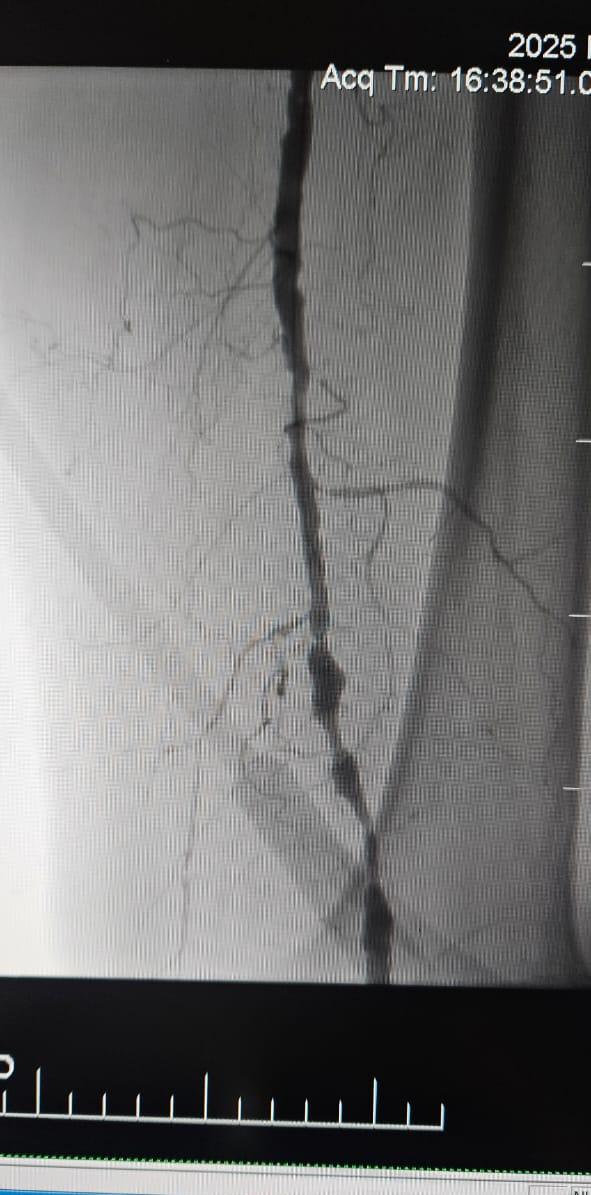

Nous sommes heureux de partager un cas réussi dans un hôpital de Batumi, en Géorgie, où une patiente de 78 ans atteinte d'ischémie critique des membres (ILC) causée par une occlusion totale chronique de l'artère du membre inférieur a montré une amélioration clinique remarquable après un traitement avec le système de cathéter de dilatation à ballonnet ThorCrack Peripheral IVL.

Ce cas souligne la valeur clinique de la lithotripsie intravasculaire (IVL) dans le traitement des cas CLI complexes avec une occlusion chronique à long segment-en particulier chez les patients présentant une calcification lourde, où les ballons traditionnels ou les dispositifs d'athérectomie peuvent avoir une efficacité limitée.